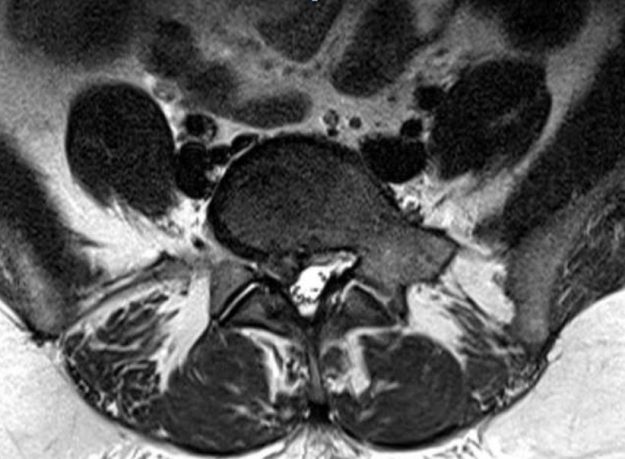

Ασθενής άδρας 33 ετών με έντονη οσφυαλγία απο 12μήνου και επιδείνωση από διμήνου. Ο απεικονιστικός έλεγχος ανέδειξε σπονδυλολίσθηση 2ου βαθμού σε έδαφος σπονδυλόλυσης στο ύψος Ο5-Ι1. Διενεργήθη διαδερμική (ελάχιστα επεμβατική) σπονδυλοδεσία στο επίπεδο Ο5-Ι1 Ο ασθενής παρουσίασε σημαντική βελτίωση της συμπτωματολογίας του. Εξήλθε του νοσοκομείου την 3η μετεγχειρητική ημέρα. Προεγχειρητική Αξονική Τομογραφία Μετεγχειρητική Αξονική Τομογραφία…